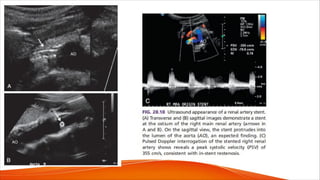

FIG. 28.16 (A and B) Pulsed Doppler

demonstrates elevated peak systolic

velocity (PSV, 315.5 cm/s)

at the origin of the main left renal

artery (LRA) with tardus-parvus

waveforms in the segmental

branches of the renal artery (arrows

in B). (C) Pulsed Doppler images

after stent placement show

normalization of the PSV (52.1 cm/s)

in the stented segment. (D)

Waveforms from the left midpole

(MP) segmental artery demonstrate

a return to normal appearance with

rapid upstroke and

waveform shape (arrows) Note the

return of the early systolic

compliance peaks (arrowheads).

KID, Kidney; LT, left; SEG, segment;

UP, upper.